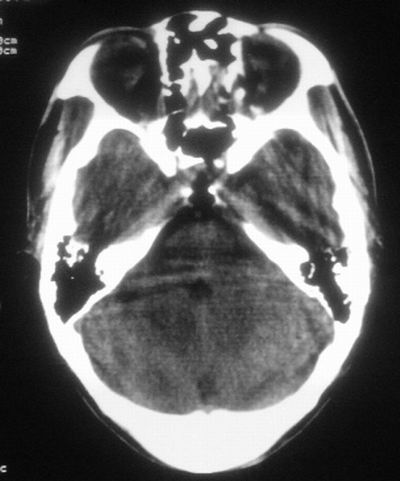

患者,男,30岁,右侧面部麻木,右上肢活动受限27小时。pe:神清、呼吸平稳,口角左歪,右上肢活动受限,右手掌握力消失,右侧躯体痛觉减退。

第一次颅脑ct扫描:左侧额顶叶血肿。